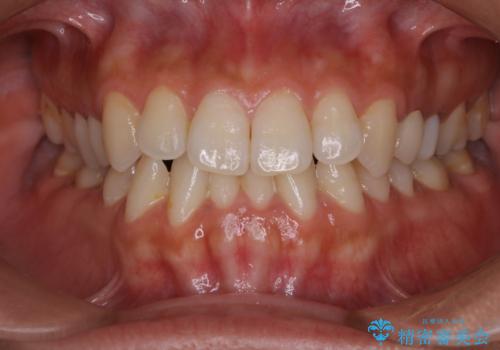

海外へ行く前にクリーニングできれいにしたい

- 長期で海外へ行くため、全体的にきれいな状態にしてほしいとのことでした。PMTC60分コースを行いました。